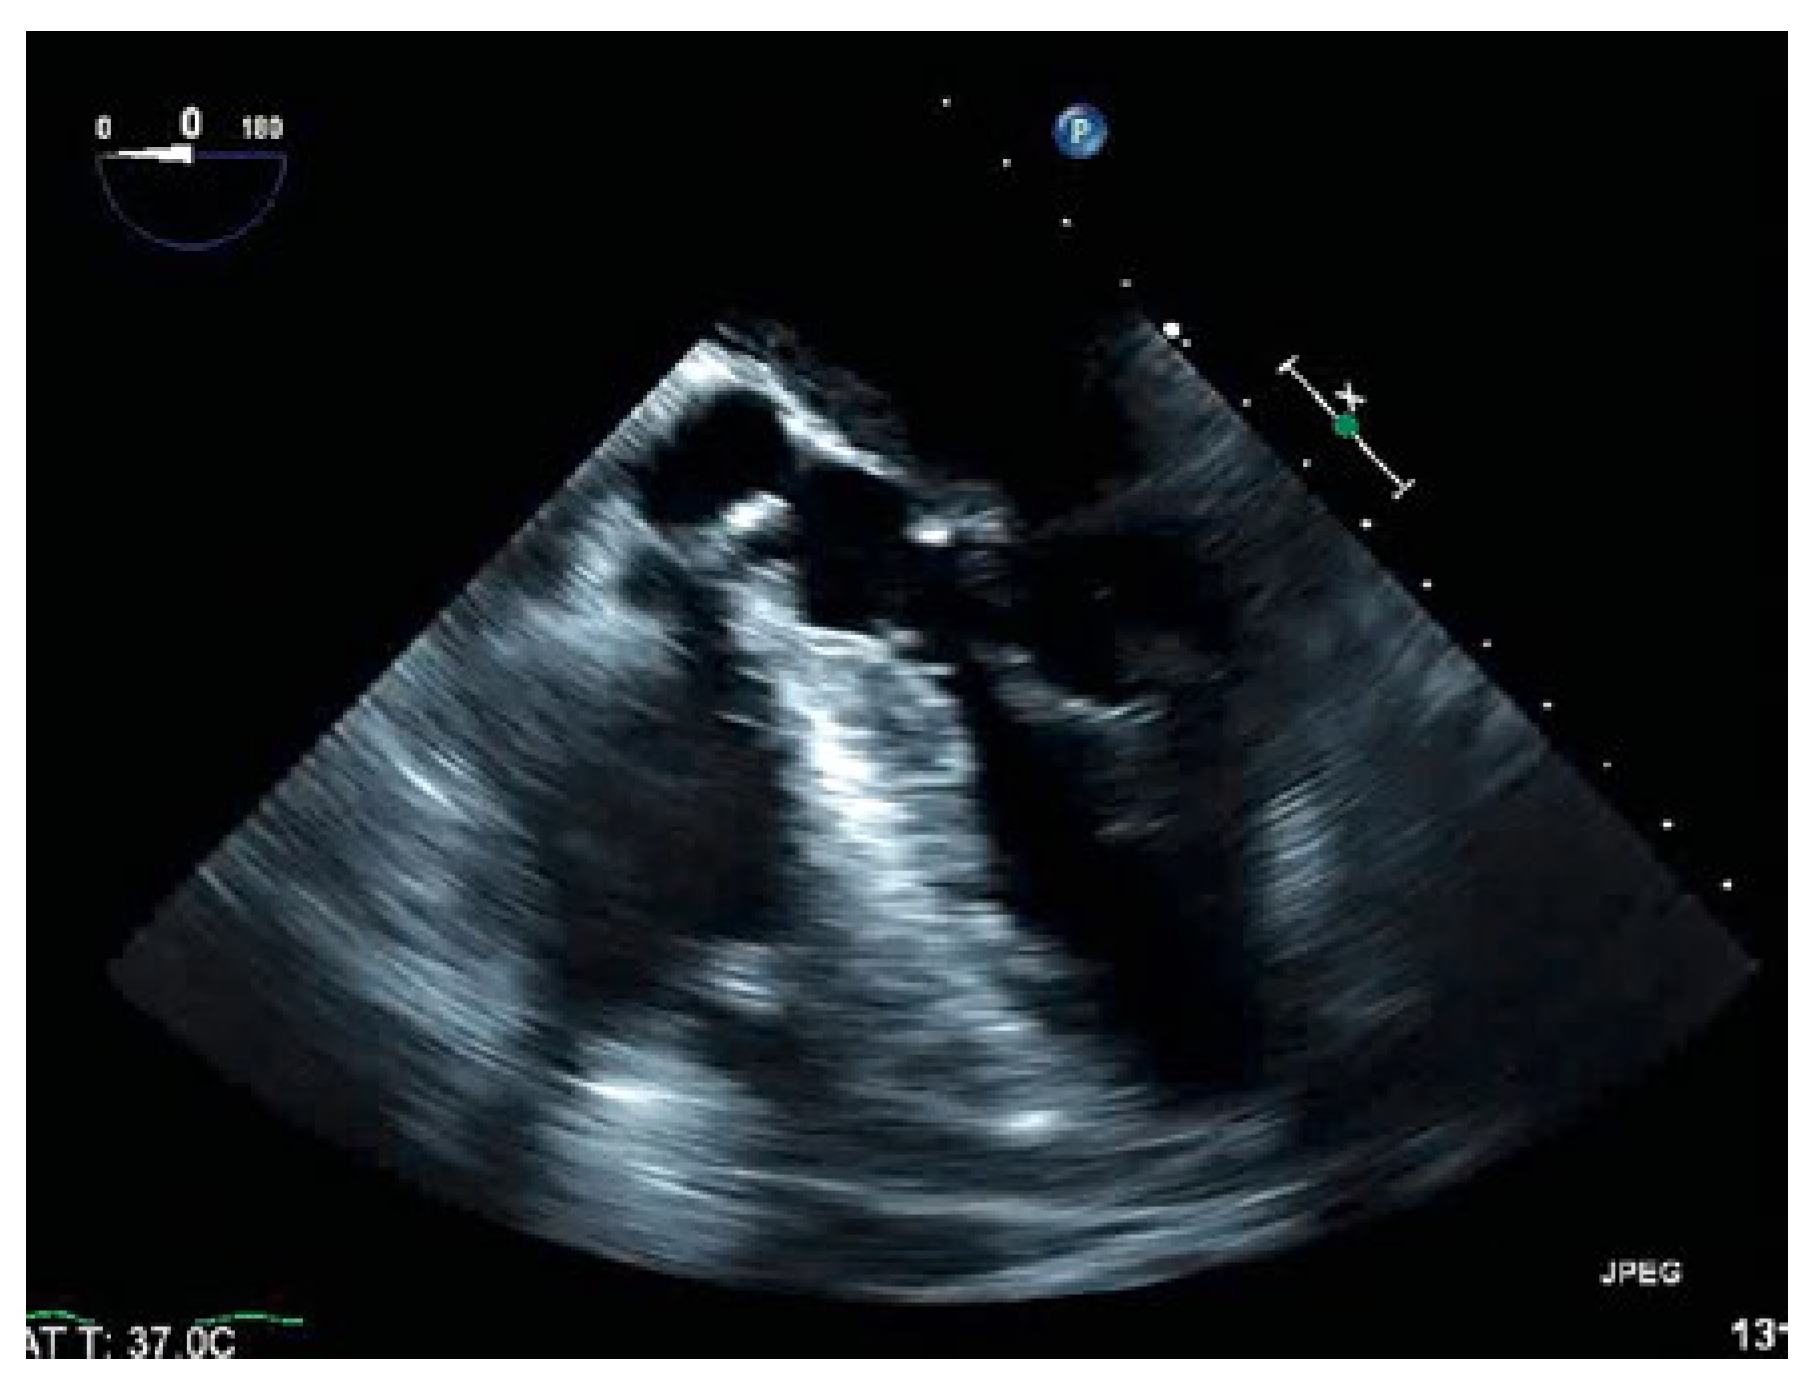

Thrombus in Transit

Case presentation